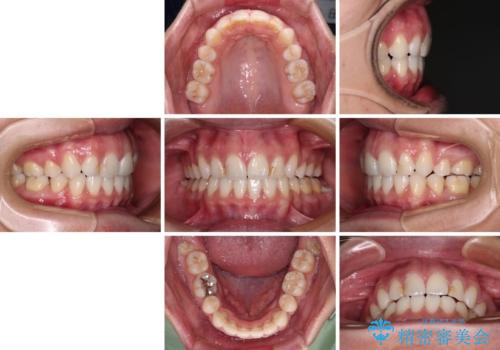

- くちばしのような前歯の突出感を気にして来院された患者様です。

上下左右第一小臼歯4本を抜歯して、積極的に口元を引っ込めるよう、ワイヤー装置にて矯正治療を行うこととしました。

抜歯矯正を行ったことで、顎先のつっぱり感や口元の閉じにくさを解消することができました。